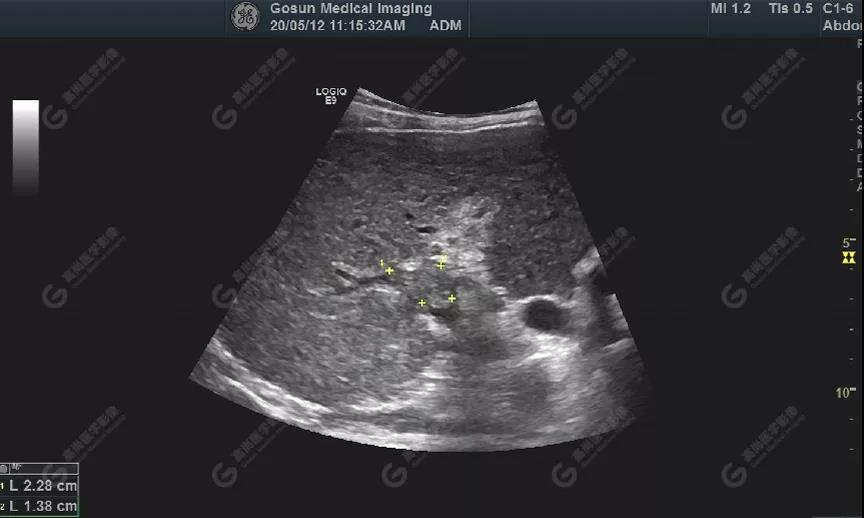

肝包膜不光滑,內(nèi)部回聲增粗、分布不均勻

門靜脈右支管腔內(nèi)見大小約23mm×14mm實性低回聲充填